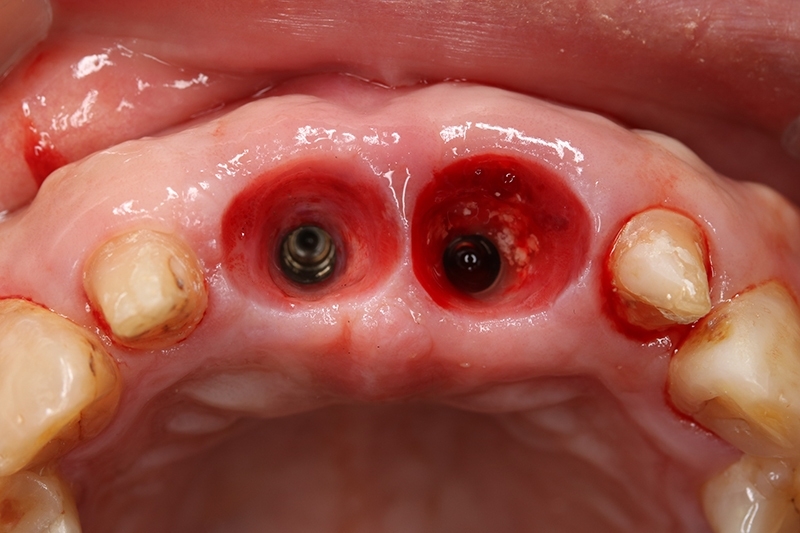

可見植體移除後骨缺損範圍大

可見骨頭生長良好

水平增寬的骨頭,這樣植牙才有理想的三度空間可以置放